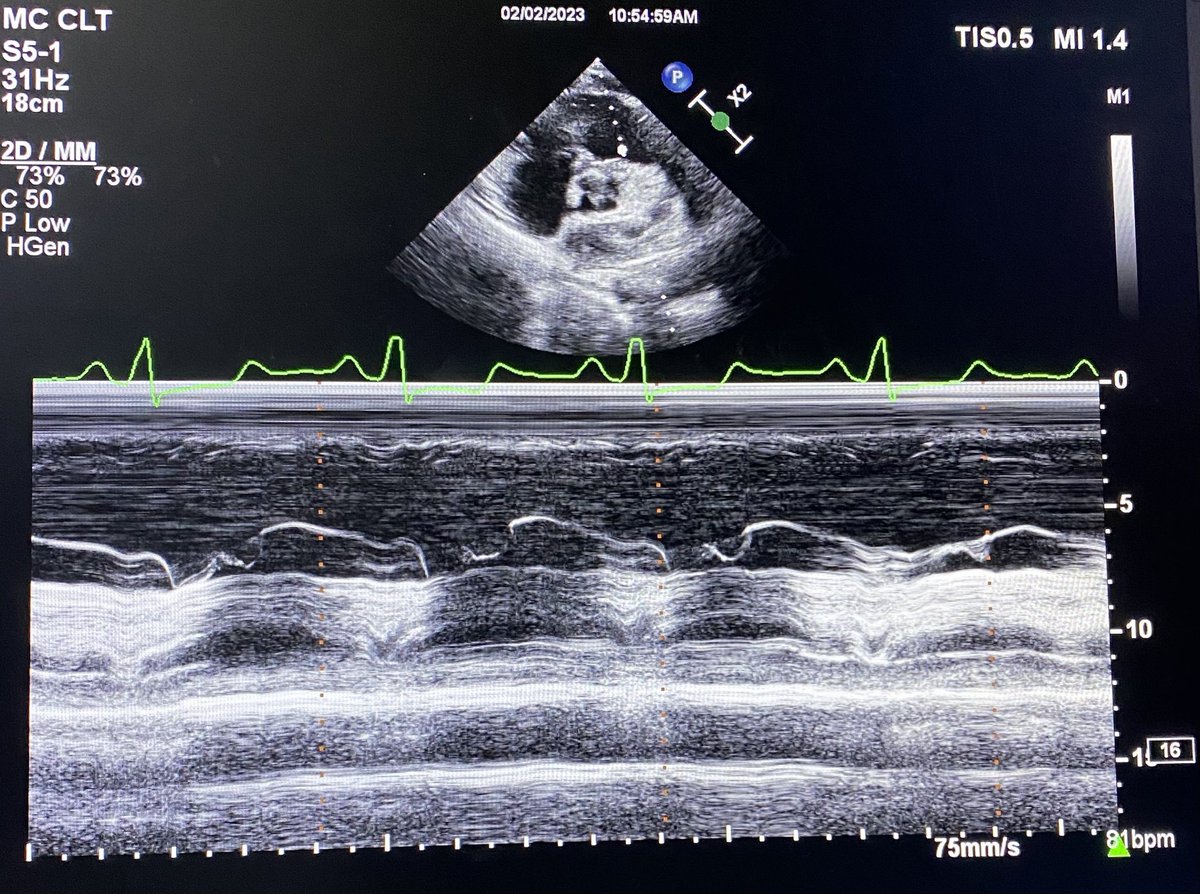

Simple quiz for residents. One hemodynamic finding from this M mode of pulmonary valve